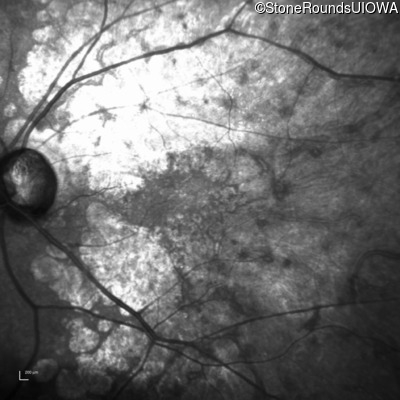

Infrared Fundus Photograph - Right - 20/25 -1

Exemplar